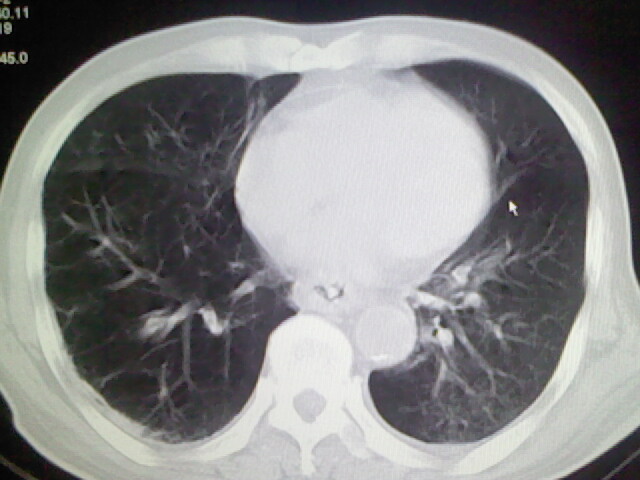

男,70岁,脑出血,长期卧床,左侧背部可触及肿块

右肺病灶考虑炎症性。

右肺病灶考虑炎症性

考虑右肺及左肺下叶炎症。

右肺及左肺下叶炎症。

考虑右肺及左肺下叶慢性炎症。

右侧肺部见片状密度增高影,边缘模糊。考虑炎症。另食管壁增厚。

右肺上叶前段病呈楔形,其尖端指向肺门,考虑肺动脉栓塞可能性大.